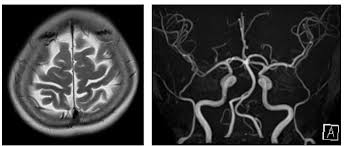

MRI(자기 공명 영상)은 강력한 자기장과 라디오파를 이용하여 체내 조직의 이미지를 생성하는 기술입니다. MRI는 연부 조직, 즉 뇌, spinal cord, 근육, 그리고 다양한 내장 장기 등을 상세하게 볼 수 있는 특징이 있습니다. 주로 신경계, 근골격계 및 종양 연구의 진단 도구로 사용됩니다.

반면에 MRA(자기 공명 혈관 영상)는 MRI의 일종으로, 혈관의 이미지를 생성하는 데 초점을 맞추고 있습니다. 이는 혈관의 구조 및 흐름을 평가하는 데 유용하며, 주로 심혈관 질환의 진단에 사용됩니다. MRA는 특히 혈관의 협착이나 막힘, 동맥류와 같은 혈관 관련 문제를 발견하는 데 매우 유용합니다.

MRI는 인체 내의 수소 원자의 자기적 성질을 이용하여 이미지를 생성합니다. 강력한 자기장이 수소 원자를 정렬시킨 후, 라디오 파를 통해 이들을 자극하여 방출되는 신호를 수집합니다. 수집된 신호는 컴퓨터에 의해 해석되어 이미지를 만들어 내는데, 이 과정에서 세부적인 이미지가 생성되어 체내 구조를 명확하게 볼 수 있게 됩니다.

MRA는 MRI의 기법을 기반으로 하므로, 기본적으로는 동일한 작동 원리를 가지고 있지만, 약간의 차이점이 있습니다. MRA는 특히 혈관을 시각화하는 데 최적화되어 있으며, 주로 조영제를 사용하여 혈관을 더욱 뚜렷하게 구분합니다. 조영제는 혈관 내에서 신호의 차이를 만들어 신호 강도를 높여줍니다. 이로 인해 혈관의 형태와 상태를 더욱 명확하게 시각화할 수 있습니다.